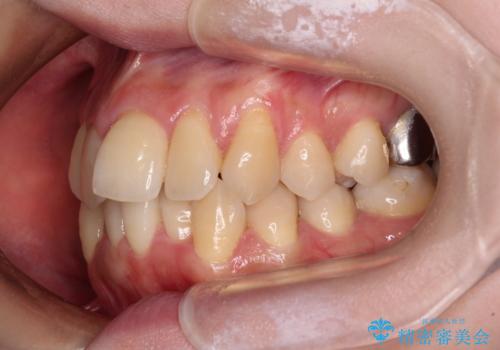

3. 【モニター】急速拡大装置 狭い歯列を拡大してワイヤー装置で短期間治療の治療後